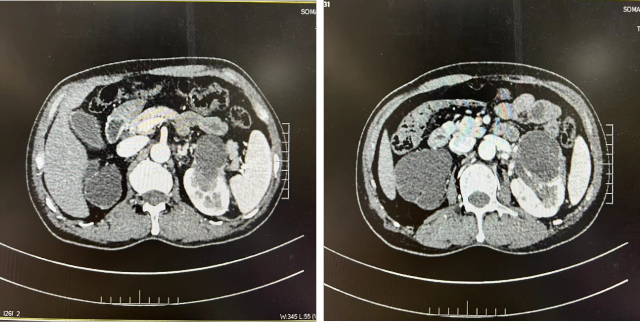

CT(2022.7):1. 右肺转移瘤切除术后改变;2. 左肾上腺结节,转移?3. 左肾多发结节,转移瘤?4. 腹膜后淋巴结肿大,转移可能;5. 左肾多发小囊肿。

CT(2023.7.17):1. 左肾上腺结节、左肾结节及肿块较前明显增大:转移?左肾 CA 并左肾内、肾上腺转移?2. 腹膜后淋巴结较前增大,转移可能;3. 余况基本同前。

2023.7 开始予以伏罗尼布单靶治疗

CT(2023.12.6):1. 左肾上腺结节较前稍缩小、左肾结节及肿块较前稍缩小;2. 腹膜后淋巴结转移灶同前;3. 余况基本同前。

伏罗尼布治疗 2 年后病变进展

CT(2025.4.7):1. 左肾上腺肿块较前明显增大;2. 左肾结节及肿块部分较前增大;3. 腹膜后淋巴结同前;4. 右侧胸膜结节状增厚较前增大,建议追踪;5. 余双肺情况基本同前。